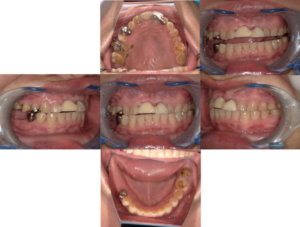

治療終了後の口腔内写真とレントゲン写真を示します。

治療終了後

左下奥歯のインプラントも同様に3ヶ月の待機期間(インプラントが骨に結合する期間)の後に、仮り歯を製作し、その後本歯に移行しました。

インプラント治療で奥歯の咬み合せができてから前歯のブリッジでの治療を行い、マウスピースを装着して歯ぎしりから防御しています。